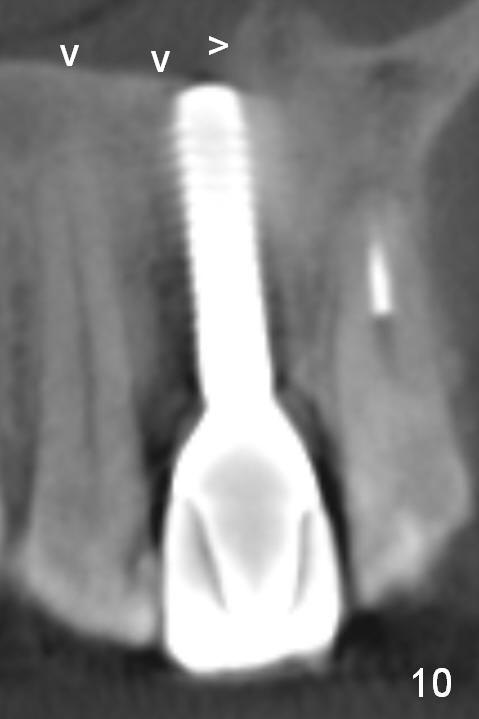

Fig.10 is a sagittal section of the implant (arrowheads: nasal floor). It is apparent that there is enough space (Fig.11,12 (PA)) for osteotomy (Fig.13 red lines: A: angled Titanium abutment). With the palatal mucoperiosteal flap attached the implant/bone segment, it is moved apically (Fig.14). Coronally the coronal portion is repositioned palatally while the apical portion buccally (Fig.15 arrows). Is the segment stable?